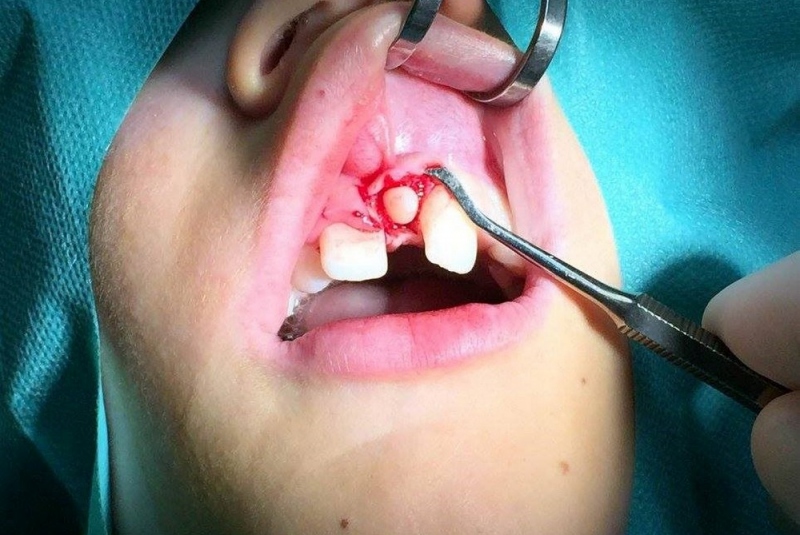

- Patefakcia (čeľustno-ortotodontické sťahovanie, zle postave- ných zubov do oblúka)

- Chirurgia detí a dorastu